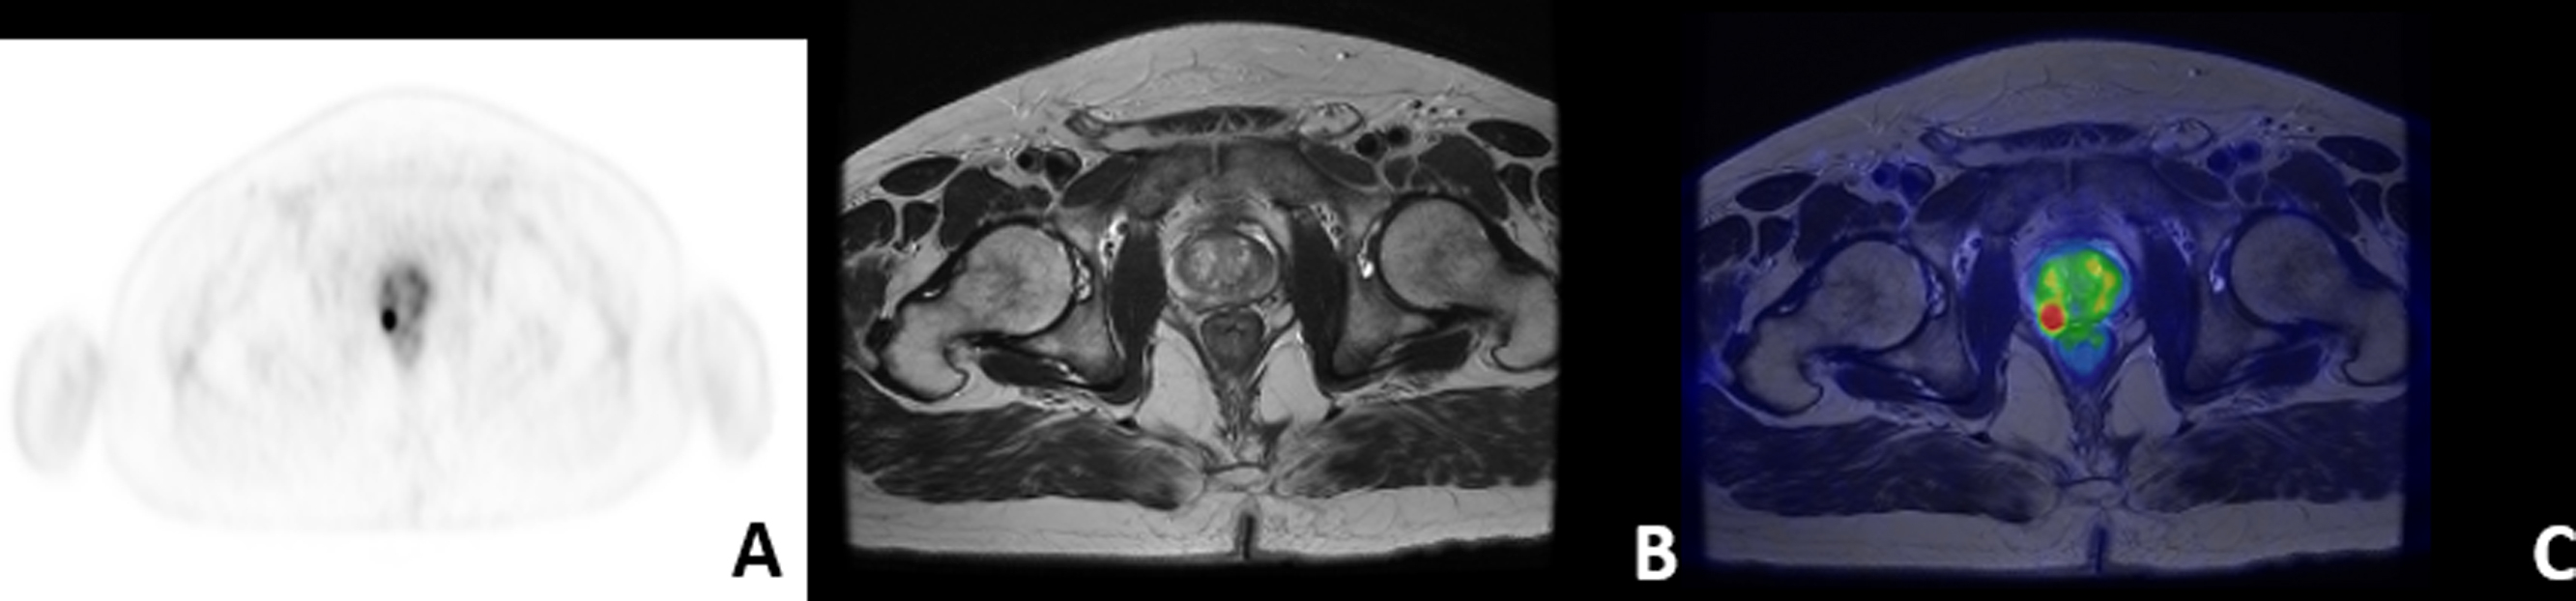

Considering that radiomics is rapidly emerging as a translational approach, and that the simultaneous acquisition of PET/MR scans offers better alignment (see Fig. 15.2 ) and direct correlation of images, PET/MR-based radiomics represents a promising methodology in the field of oncology. The easy coregistration of ROI/VOI between PET and MR imaging allows indeed to extract both functional and morphological data from the patient at the same time, facilitating the simultaneous analysis of heterogeneous and possibly synergic data in a single end-to-end approach.

Figure 15.2, PET/MRI simultaneous acquisition in PCa. (A): transaxial 68 Ga-PSMA PET; (B): Axial T2-weighted sequence; (C): 68 Ga-PSMA PET/MRI (Eudract number 2018-001034-18).